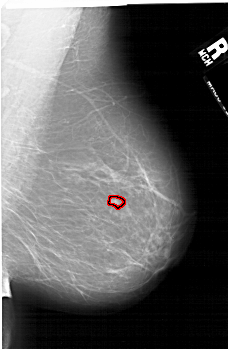

A_1499_1.LEFT_CC

LEFT_CC LINES 6841 PIXELS_PER_LINE 3721 BITS_PER_PIXEL 12 RESOLUTION 43.5 NON_OVERLAY

FILE: A_1499_1.RIGHT_MLO.OVERLAY

TOTAL_ABNORMALITIES 1

ABNORMALITY 1

LESION_TYPE MASS SHAPE LOBULATED MARGINS ILL_DEFINED

ASSESSMENT 4

SUBTLETY 3

PATHOLOGY MALIGNANT

TOTAL_OUTLINES 1

BOUNDARY